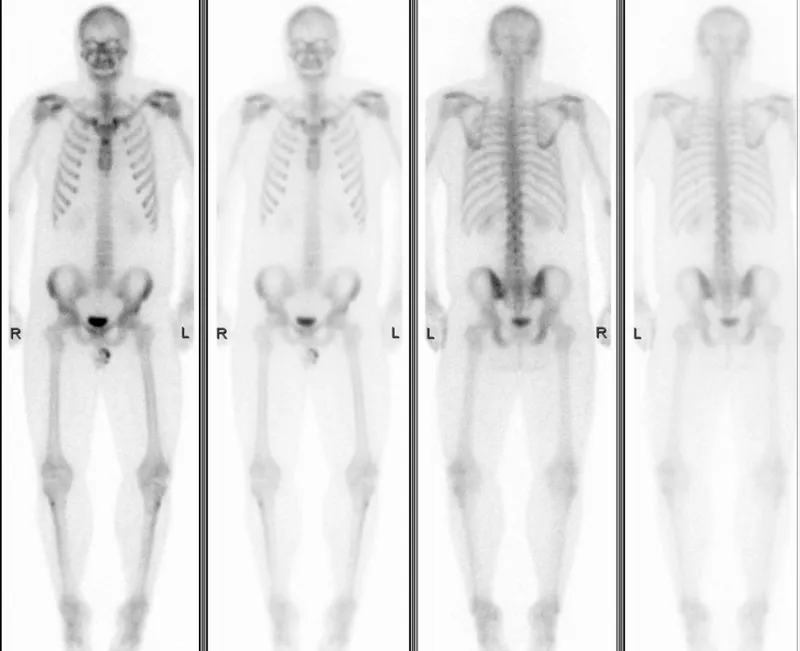

A Rare Condition Pushed Her Bones to Old Age Early

• What: A young woman with ankylosing spondylitis experiences accelerated skeletal aging, resembling an older individual.

Imagine being in your twenties, yet your body resembles that of someone much older, struggling with the fragility of brittle bones and the weight of unexplained pain. This was the reality for a young woman diagnosed with ankylosing spondylitis, a form of arthritis that primarily affects the spine. With a swift decline into frailty, researchers turned to bone density scans and intricate imaging studies to unravel how her condition fundamentally challenged the traditional understanding of disease progression. Could inflammation truly cast such a long shadow on youthful bones?

The Hidden Mechanism Behind Accelerated Aging

This young woman’s case is both astonishing and troubling. As she grappled with the debilitating effects of ankylosing spondylitis, her medical records revealed a startling picture: an accelerated aging process likened to that of a much older patient. The investigation hinged on bone density scans that illuminated what remains a debated mystery in gerontology and osteoporosis research. The long-term effects of inflammation, once considered a mere symptom of her condition, appeared to be a catalyst for premature skeletal aging, distorting the timeline of the disease.

Research underlines a complex interplay between inflammatory responses and skeletal health. Inflammation, while a natural immune response, can have drastic repercussions on the skeletal system, prompting bone loss and altering bone density far beyond what age alone would dictate. This anomaly reveals a puzzling narrative where the very mechanisms of the body, in their attempt to fight inflammation, inadvertently lead to the deterioration typically associated with old age, calling into question our fundamental understanding of how diseases impact the body over time.